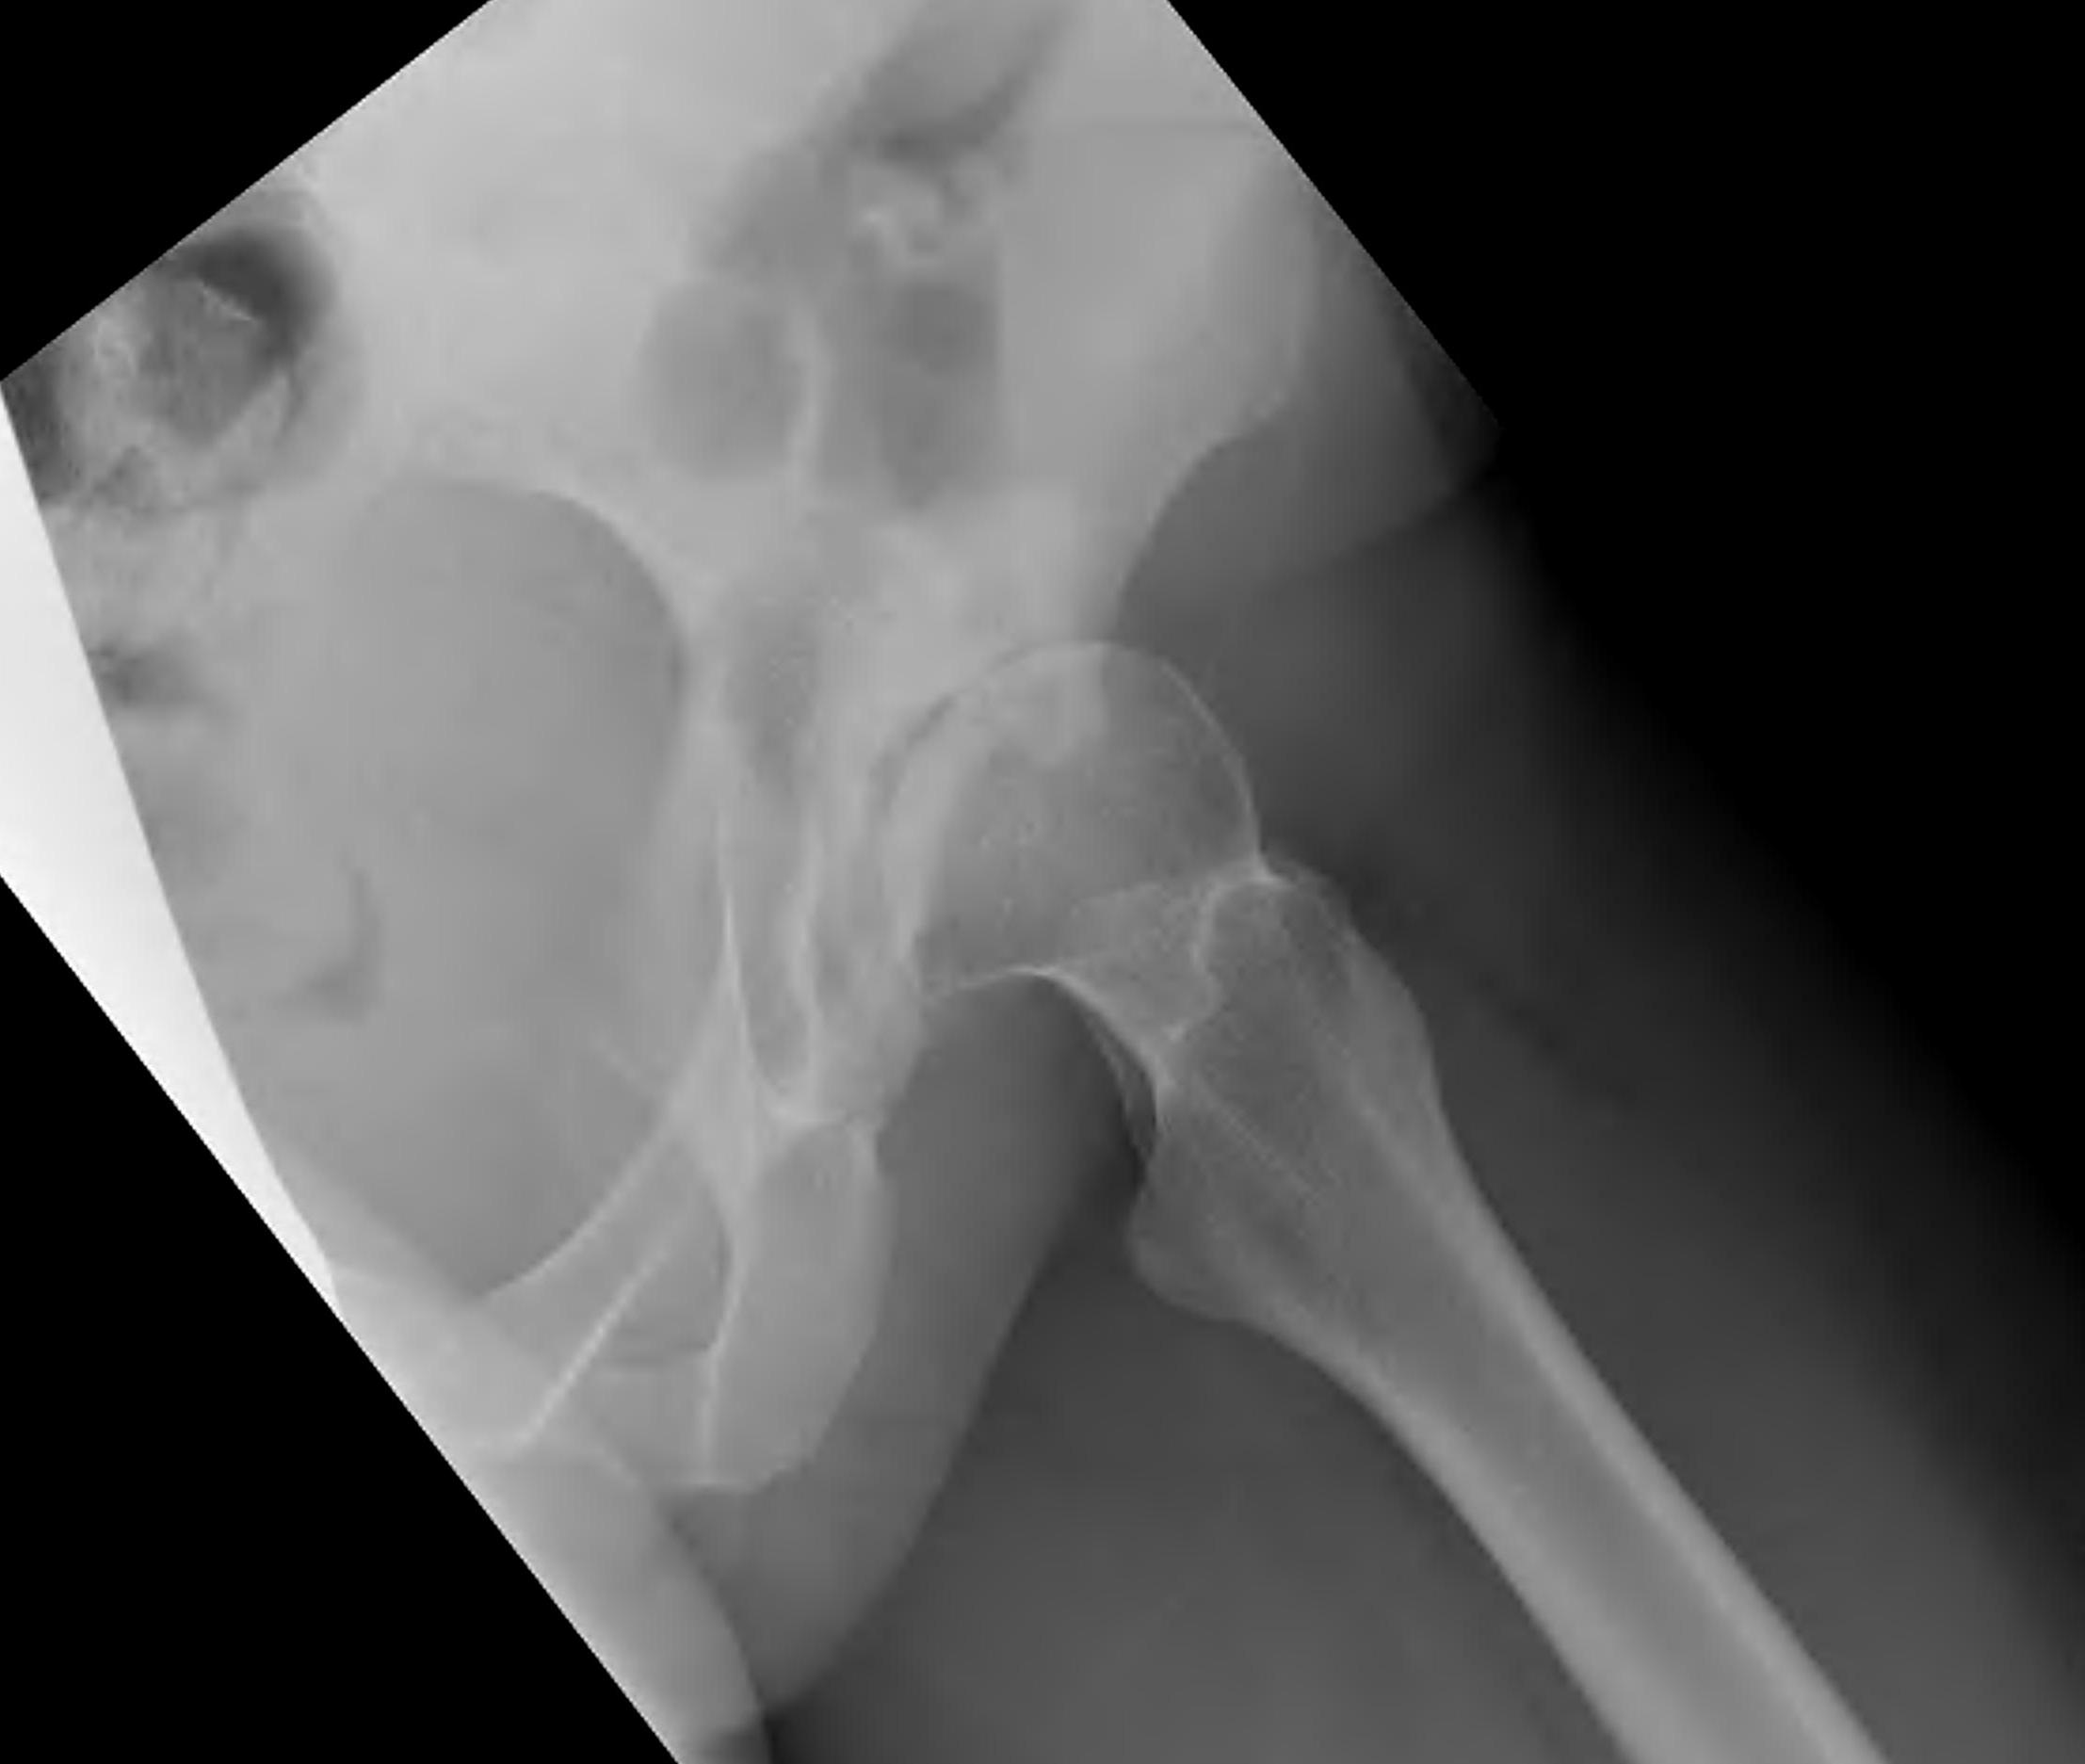

Crowe Classification

| Crowe Type | Definition |

|---|---|

| I | Subluxation < 50% vertical diameter femoral head |

| II | Subluxation 50 - 75% vertical diameter femoral head |

| III | Subluxation 75 - 100% vertical diameter femoral head |

| IV | Proximal migration of > 100% vertical diameter femoral head |

Crowe I

Crowe II

Crowe III

Crowe IV